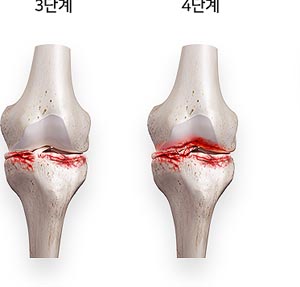

퇴행성 관절염은 나이가 들면서 자연스럽게 발생하는 관절의 마모로 인해 많은 사람들이 고통을 겪고 있는 질환입니다. 통증과 불편함 때문에 일상 생활에 큰 지장을 주기도 합니다.

약물 치료와 수술

심한 경우에는 약물 치료나 수술이 필요할 수 있습니다. 비스테로이드 항염증제(NSAIDs)는 통증과 염증을 줄이는 데 효과적이며, 경우에 따라 스테로이드 주사를 고려할 수 있습니다. 마지막으로, 관절이 심하게 손상된 경우 관절 치환술 같은 수술적 방법이 필요할 수 있습니다. 이러한 방법은 의사와 상담하여 결정하는 것이 중요합니다.